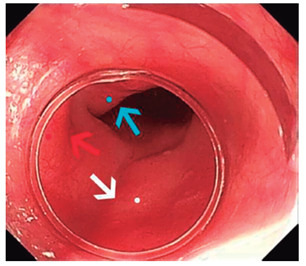

Paso 3, identificación de los reparos anatómicos: cricofaríngeo, arco aórtico y bronquio fuente izquierdo, EEI y silueta de la columna vertebral, que a su vez se puede corroborar instilando 30 mL agua en la luz esofágica, observando el área de declive (Figura 1).

Paso 6, túnel submucoso: se fabrica el túnel submucoso con electrobisturí en modo spray coagulation, hasta sobrepasar 3 cm distal al cardias en el eje de las 5 y realizando la disección muy cercana a la capa muscular circular, la cual debe visualizarse totalmente horizontal (inferior) al eje del endoscopio y teniendo máximo cuidado de no lesionar la mucosa esofágica (Figura 2 C ). Es de utilidad retirar el endoscopio en varias ocasiones del túnel submucoso, introduciéndolo en la luz esofágica para verificar que la disección se esté realizando en el eje de las 5 y para confirmar cuando la disección supere el EEI, lo cual se complementa observando el cardias en retroflexión y siguiendo la columna del índigo carmín.

Los resultados postoperatorios se encuentran en la Tabla 2. Se encontró que 3 de 4 pacientes fueron operadas por vía posterior, debido a que se considera esta ruta más práctica al momento de realizar la miotomía, dado que la salida del electrobisturí se ubica en el eje de las 6 del equipo, quedando la cámara hacia las 12, lo que permite una mejor visualización del plano muscular a seccionar (Figura 3); solo el POEM 1 se realizó por vía anterior, hacia las 2 del reloj, lo que resultó en mayor tiempo y grado de dificultad en comparación con los otros 3 pacientes (POEM 2-4). En todos los pacientes se presentaron eventos derivados de la miotomía y la presión del CO2, el más común fue el capno/neumoperitoneo, este evento se manejó durante el intraoperatorio con un yelco 14G, localizado en el flanco derecho y conectado a una trampa de agua, sin complicaciones. Una de las pacientes presentó neumotórax izquierdo, el cual se manejó con un tubo de toracostomía 28 Fr a sistema de drenaje cerrado y retirado 24 horas después, posterior a la realización de una radiografía de tórax que evidenciaba la resolución del neumotórax, es por esto que la paciente (POEM 3) tuvo una estancia hospitalaria mayor que el resto de pacientes, el enfisema subcutáneo no requiere manejo adicional, debido a que es autolimitado.

Nuestros resultados coinciden con la literatura mencionada, en los que se muestra una evidente mejoría del Eckardt y la presión del EEI, aunque se trata de una muestra pequeña. En la población estudiada hubo una paciente con MHL previo y posteriores dilataciones, lo cual le agregó al procedimiento un mayor grado de dificultad, debido al proceso fibrótico; sin embargo, esta es la circunstancia en la que tiene mayor utilidad la miotomía por vía posterior, debido a que el plano de disección se visualiza más claramente (Figura 4) 5,22.

Para los casos difíciles como, por ejemplo, pacientes con Heller, dilataciones y/o que han recibido toxina botulínica, que distorsionan la anatomía del EEI, puede utilizarse un segundo endoscopio, siendo este de diámetro pediátrico (Figura 3). En nuestros casos no hubo la necesidad de realizarlo, pero se puede lograr una longitud mayor de la miotomía gástrica con este método (3,2 cm frente a 2,5 cm; p = 0,013) y menor índice de perforaciones a nivel de mucosa gástrica; sin embargo, no se obtiene un impacto significativo en el éxito de la técnica 23.